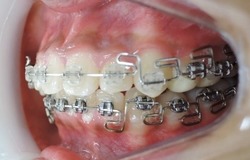

大人の矯正治療は出来るだけ見えにくい小さな矯正装置を利用して上の歯並びから歯ならび治していきます。埋伏している犬歯も萌出させていきます。

上顎の歯列がある程度改善してから下顎の歯列を見えにくいブラケットという矯正装置で整えていきます。埋伏している犬歯も萌出させていきます。

MEAW(マルチループ)により咬合高径(咬み合わせの高さ)を改善して美しい咬み合わせに治療していきます。(矯正開始から3カ月後)

終了時2か月前(1年3ヶ月後)

終了時(開始から1年8カ月後)